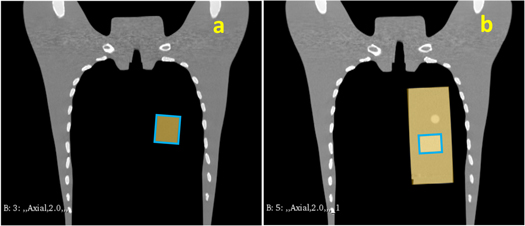

2.2. Phantom simulation

Phantom simulations were implemented to test the workflow under a basic condition: steady BV with only shifted VOI and no unknown or complex motions. Two scenarios were simulated, both using chest phantoms: (1) phantom N-1 (Kyoto Kagaku Co., Ltd, Kyoto, Japan) inserted with a customized cuboid phantom as the clinical target volume (CTV) (figure 2(a)), and (2) a cylindrical four-dimensional CT (4DCT) imaging insert of the QUASARTM (Modus Medical Devices Inc. London, Canada) with the relatively high-density region as the CTV (figure 2(b)). Two CT scans of the chest phantom were performed in each scenario; the first scan was considered the PlanCT, and the second was considered the in-room CT containing manually shifted insertions with approximately 20 mm in the superior direction. The cuboid or cylindrical insertions were set as the VOI, and the remaining CT volume was considered the BV (figure 2).

Figure 2. Illustration of Scenario 1 (a) and 2 (b), the yellow regions represent the volume of interest (VOI), and the blue rectangular areas represent the clinical target volume (CTV).

Standard image High-resolution imageBone matching (BM; figure 3(a)) and tumor matching (TM; figure 3(b)) are the two common methods of patient positioning correction adopted in clinical practice to determine the isocenter for irradiation of the day (Abe et al 2017). The dose distribution of the original treatment plan generated from the XiO-N® treatment planning system (Elekta Sweden; Mitsubishi Electric, Japan) was recalculated on the in-room and DVM CTs with different isocenters based on BM or TM to obtain the dose distributions for comparison. In addition, the dose distribution of the original plan was recalculated on the DVM CT with the isocenters calculated by the VOI and BV shifts to obtain the dose distribution of the DVM CT with the isocenter based on TM, which was DVM-TM, and that based on BM was DVM-BM. The dose distribution of the in-room CT with the isocenter based on TM was named InRoom-TM, and that on BM was InRoom-BM.

Figure 3. Illustration of bone matching (a) and tumor matching (b) for Scenario 1. The red dots represent the isocenter.

Download figure: